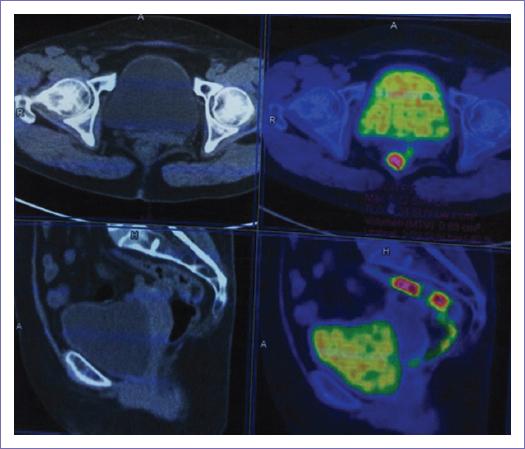

Al no encontrar datos de actividad tumoral en otro sitio y para descartar el origen metastásico de la lesión, se decide completar protocolo diagnóstico con tomografía por emisión de positrones (PET) con TC helicoidal multicorte y flúor 18-fluorodesoxiglucosa (PET/CT F18-FDG) que mostro un cérvix con zona focal de metabolismo en relación con actividad tumoral con SUVmáx (valor máximo estandarizado de captación) de 5.2 y un quiste dependiente de ovario derecho sin metabolismo (Fig. 5).

Figura 5 Tomografía por emisión de positrones/tomografía computarizada con flúor 18-fluorodesoxiglucosa que muestra una zona focal de metabolismo con valor máximo estandarizado de captación 5.2 a nivel del cuello uterino en relación con la actividad tumoral.

En el caso de la PET/CT F18-FDG para evaluación del origen primario de la lesión en el cérvix, cabe mencionar que se reporta una sensibilidad menor al 60% para la evaluación de neoplasias productoras de mucina por la baja captación de F18-FDG. Stahl, et al. reportaron esta baja captación en 40 pacientes con carcinoma gástrico localmente avanzado y 10 sujetos control, valorando cualitativamente y cuantitativamente la captación de FDG con respecto al tipo histopatológico del tumor por la presencia intracelular y extracelular de mucina9.

La realización de la PET/CT F18-FDG no se recomienda como único estudio diagnóstico o de primera instancia, por su baja sensibilidad, sin embargo puede ser útil en el diagnóstico cuando se han realizado otros estudios de imagen, así como estudios endoscópicos, sin encontrar otros sitios de sospecha de actividad tumoral y se quiere demostrar la captación a nivel del cérvix sin actividad metabólica en otras estructuras (como se llevó a cabo en el diagnóstico de nuestro caso).